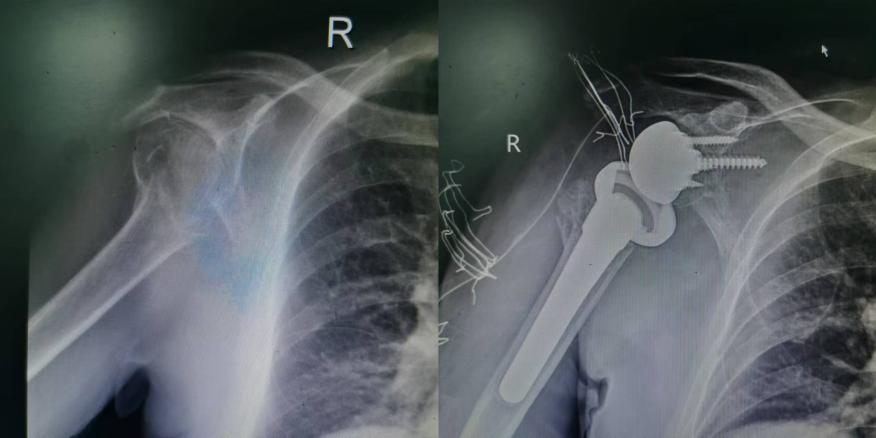

陈老师已退休多年,今年年初不慎摔倒导致右侧肱骨外科颈骨折,外院就诊后考虑患者年龄和骨折移位情况,建议保守治疗。但随着骨折畸形愈合,陈老师发现右胳膊完全抬不起来,导致平时吃饭、洗漱、梳头这些最普通的动作都成了奢望。为了解决这个问题,陈老师到我院关节外科就诊。在对患者进行仔细检查后,王坤正教授考虑陈老师是骨折畸形愈合伴巨大肩袖撕裂,建议行反肩关节置换术,来改善目前肩关节的功能。最终在杨佩主任、田润副主任、孔宁医生配合下,陈老师右侧反肩关节置换术顺利完成,并在关节外科医护和康复科合作下,开始进行康复治疗。